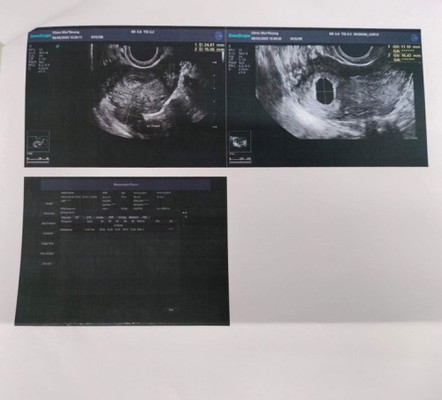

เป็นคนประจำเดือนมาไม่ตรงกันนะคะ ประจำเดือนเรามาวันที่ 12 ธ.ค หายเป็นวันที่ 16 ธ.ค มีอะไรกับแฟน 18 ธ.ค แล้วก็วันที่ 22 ธ.ค หยุดทำการบ้านไปพักหนึ่งเพราะไอมาก ต้องกินยาพวกฆ่าเชื้อแกไอก่อน แล้วก็มามีอะไรกันอีกทีวันที่ 22 ม.ค กับวันที่ 29 ม.ค หลังจากนั้นรู้สึกเวียนหัวมาก เลยซื้อที่ตรวจมาตรวจวันที่1ก.พ ขึ้นสองขีดค่ะ วันที่8ก.พ.เลยไปฝากครรภ์ที่คลินิก คุณหมอลองคร่าวๆถ้านับจากวันที่หมดประจำเดือน น่าจะเกือบ2เดือนแล้ว คุณหมอเลยซาวด์ผ่านช่องคลอดเจอถุงการตั้งครรภ์ในมดลูกแล้วค่ะ แต่ว่ายังไม่เจอตัวเด็ก หมอเลยนัดรอีก3อาทิตย์ค่อยไปตรวจใหม่เพื่อดูตัวน้องค่ะ แม่ๆท่านอื่นเคยเป็นแบบนี้ไหมคะ